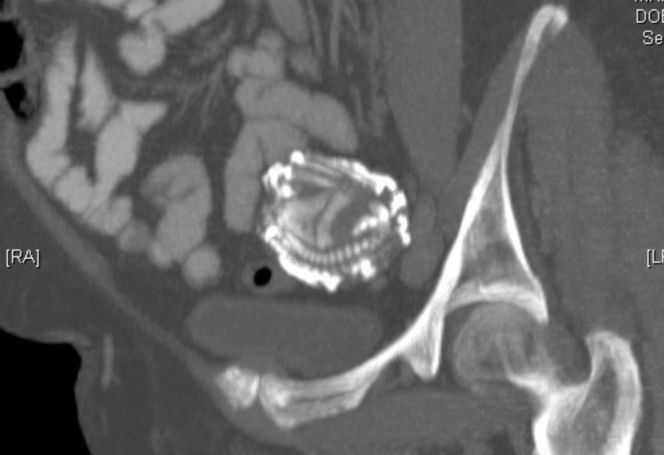

Przypadki „dzieci z kamienia” opisywano już w X wieku